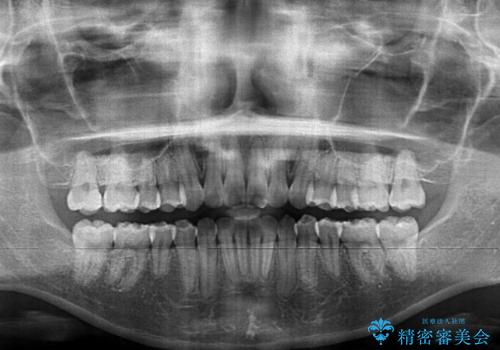

骨格的な左右差があったため、上下の正中を合わせることは困難かと思われましたが、何とか合わせることができました。

一方、骨格の差は改善できないため、奥歯の咬み合わせに物足りなさを感じました。

奥歯の咬み合わせによる不自由はなく、患者様に大変満足していただきました。